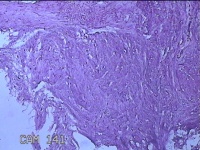

右膝前瘢痕增生组织

性别

女

年龄

38岁

临床诊断

右膝前瘢痕增生

一般病史

右膝前外伤后瘢痕增生4年余。

标本名称

大体所见

灰白粉红色组织6.5x5x1.8cm一块,表面光滑,切面灰白粉红色,质软。